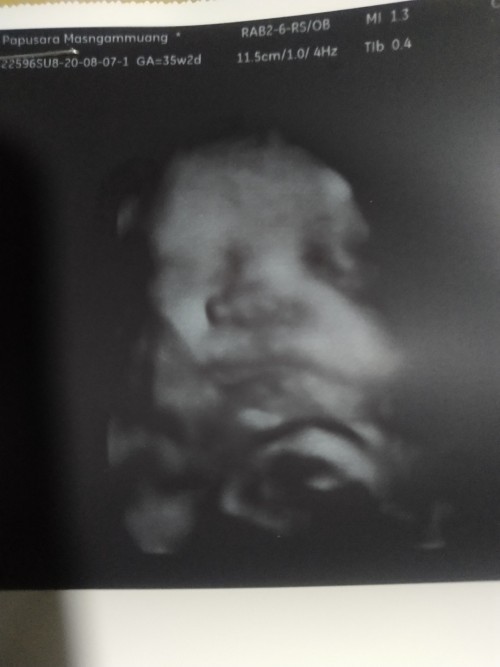

มาอวดรูปตอนซาวด์กันหน่อยค่ะ แม่ๆกำหนดคลอดเดือนไหนบ้างคะ